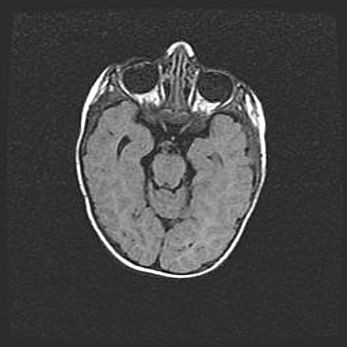

Лейкомаляция с кистозно-глиозной дегенерацией головного мозга.

Возраст: 2 месяца 25 дней

Вес: 6400 г

Окружность головы: 40 см

Срок гестации: 41 неделя

Лейкомаляцию относят к ишемически-гипоксическим повреждениям головного мозга, диагностируемым у новорожденных. При лейкомаляции в головном мозге обнаруживают очаги некроза, возникшие после тяжелой гипоксии и нарушения кровотока. В процессе морфогенеза очаги проходят три стадии: 1) развития некроза, 2) резорбции и 3) формирования глиозного рубца или кисты. Перивентрикулярная лейкомаляция (ПЛ) встречается примерно в 12% случаев среди новорожденных, обычно – у недоношенных детей, причем, частота ее зависит от массы, с которой младенец появился на свет. Наибольшее число малышей страдает лейкомаляцией, если масса при рождении 1500-2500 г.